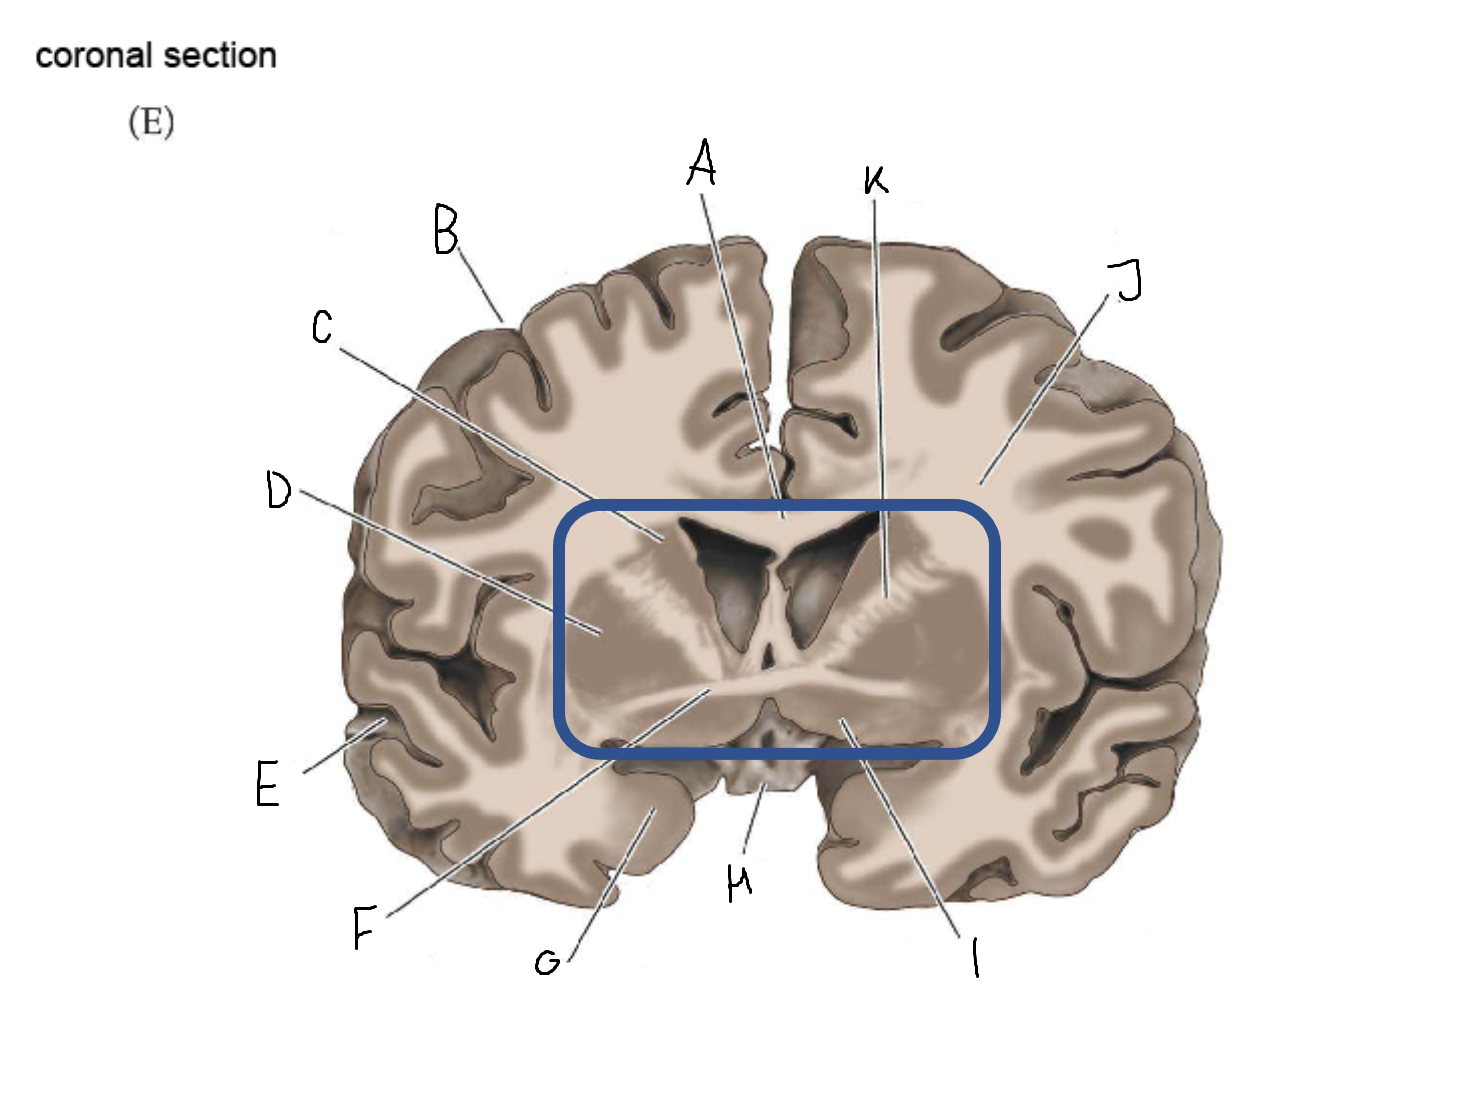

B

anterior horn of lateral ventricle

C

head of caudate nucleus

D

internal capsule (anterior limb)

E

putamen

F

globus pallidus

G

Thalamus

H

External capsule

I

internal capsule (posterior limb)

J

tail of caudate nucleus